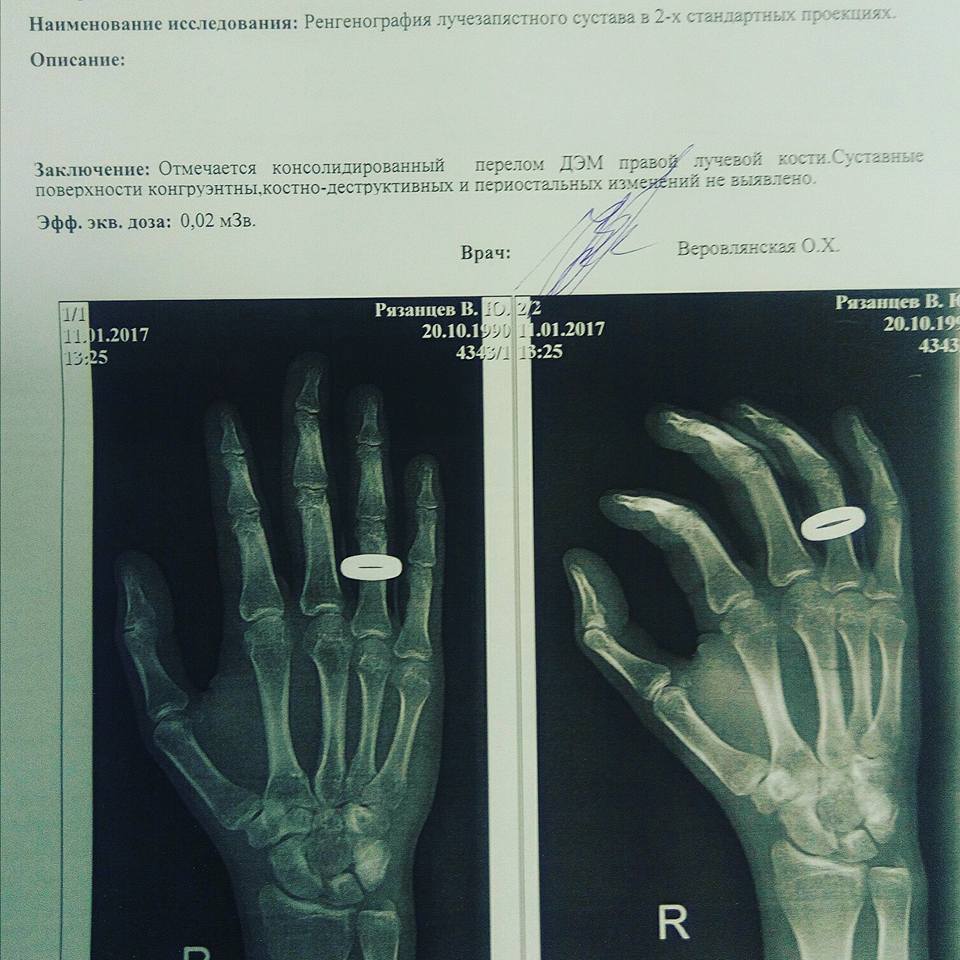

В своем заключении врачи отметили, что у Рязанцева диагностирован перелом. Фото Владислава Рязанцева. “В поликлинике рентген показал, что у меня есть перелом кисти правой руки. Четыре года назад у меня в этом же месте была травма. Врачи говорят, что, возможно, после избиения старый перелом дал о себе знать. Рука сейчас не сгибается, не разгибается, а общее самочувствие является неудовлетворительным”, - добавил Рязанцев.

В заключении врачей  говорится о том, что у Рязанцева диагностирован перелом. Заключение сделано на основе рентгеновского снимка. “Отмечается консолидированный перелом ДЭМ правой лучевой кости”, - говорится в заключении, копия которого имеется в распоряжении “Кавказского узла”.